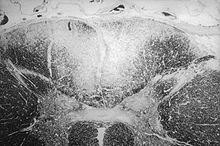

Fritz Schaudinn und Erich Hoffmann gelang 1905 der erste mikroskopische Nachweis der Treponemen, die Reinzüchtung des Syphiliserregers erstmals 1911 dem japanischen Bakteriologen Noguchi Hideyo. Der Japaner war es auch, der zwei Jahre später erstmals einen Zusammenhang zwischen der Infektion mit Treponema pallidum und der progressiven Paralyse sowie Tabes dorsalis herstellen konnte, da er die Treponemen im Gehirn und im Knochenmark nachgewiesen hatte.